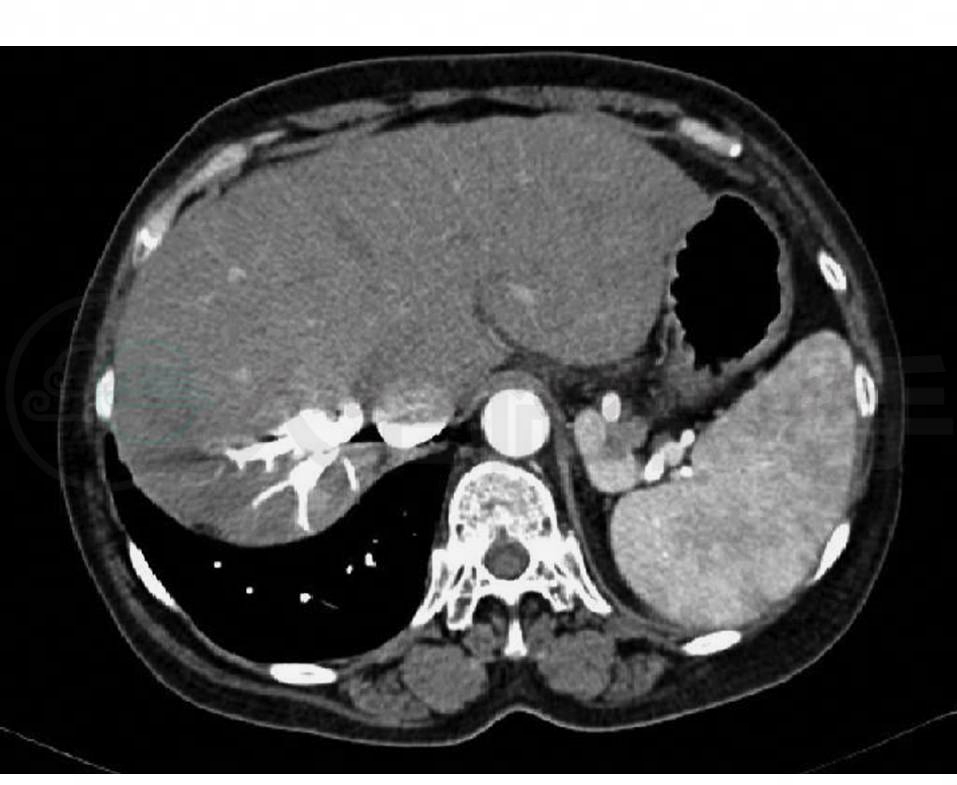

腹部增强CT三维血管重建:肝硬化,脾大;肝静脉及下腔静脉增粗(图1);胆囊多发结石。

图1 腹部增强CT三维血管重建

下腔静脉及肝右静脉分支明显增粗